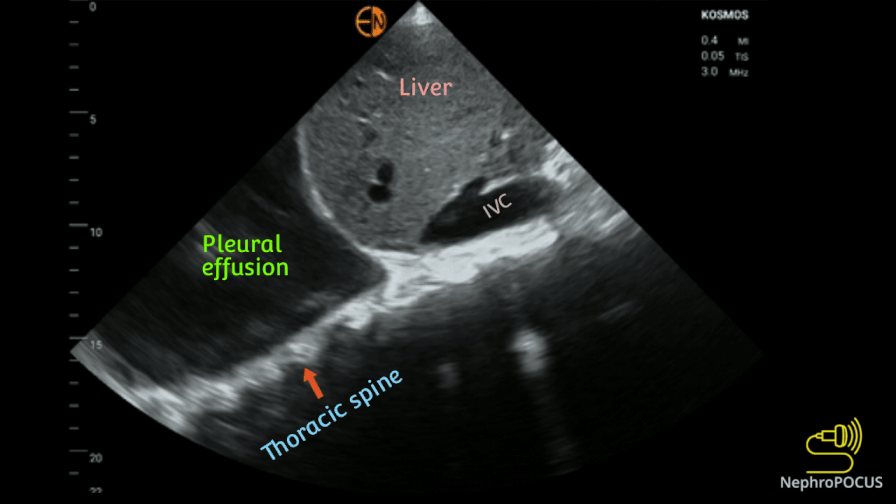

Pleural effusion: The ‘Spine sign’

Spine sign: visualization of the vertebral bodies in the thoracic cavity above the diaphragm – indicative of pleural effusion.

In the absence of pleural effusion, the spine is obscured by air in the lung, and is cut off at the diaphragm. Because fluid is a good transmitter of sound waves, spine is seen when there is fluid around the lung.

Increase the depth of the image to visualize the sign better.

While moderate to large effusions are obvious, spine sign particularly helps to detect small effusions with debris or clotted blood. Following is an example.